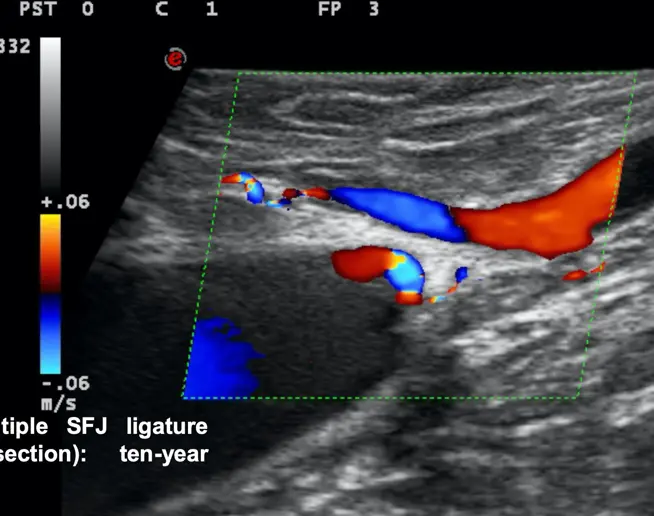

A century later Claude Franceschi took over the hemodynamic approach and developed complementary concepts thanks to the Doppler Ultrasound vascular investigation he pioneered and published in the very first book in 1977 as well as the first vascular Ultrasound imaging book in 1986. He studied fluid mechanics to understand his observations, then he proposed a hemodynamic model of venous pathophysiology.

The acronym C.H.I.V.A. stands for “cure Conservatrice et Hemodynamique de l’Insuffisance Veineuse en Ambulatoire": conservative and hemodynamic treatment of venous insufficiency in out-patients. This treatment was proposed by Claude Franceschi in October 1988 at a scientific meeting in Précys-sous- Thil. It represents a therapeutic approach to treating Chronic Venous Insufficiency (CVI) of the lower limbs in outpatients, with a focus on preserving the venous system and the Great Saphenous Vein (GSV) while ensuring the restoration of tissue drainage. (scegliere foto)